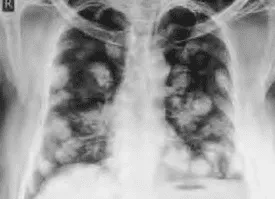

Hình ảnh “Di căn phổi bóng bay trên X-quang”.

- Ung thư nguyên bào nuôi (Choriocarcinoma). Tân lập ác tính toàn tế bào nuôi, không còn gai rau; Khởi phát sau thai trứng, thai bình thường hoặc tự phát không liên quan thai kỳ (non-gestational). Di căn xa sớm (phổi, não, gan…).

- III: Di căn phổi (dù có hay không tổn thương ở tử cung hoặc cơ quan sinh dục khác).